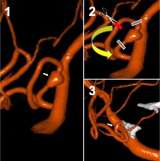

Cerebral Aneurysm Coiling

Cerebral Aneurysm Coiling - Anterior 2D angiographic view of a cerebral aneurysm (white arrow) located at the left carotid artery bifurcation (left). The cerebral aneurysm after one coil has been placed inside the aneurysm (middle) and the final image (ri